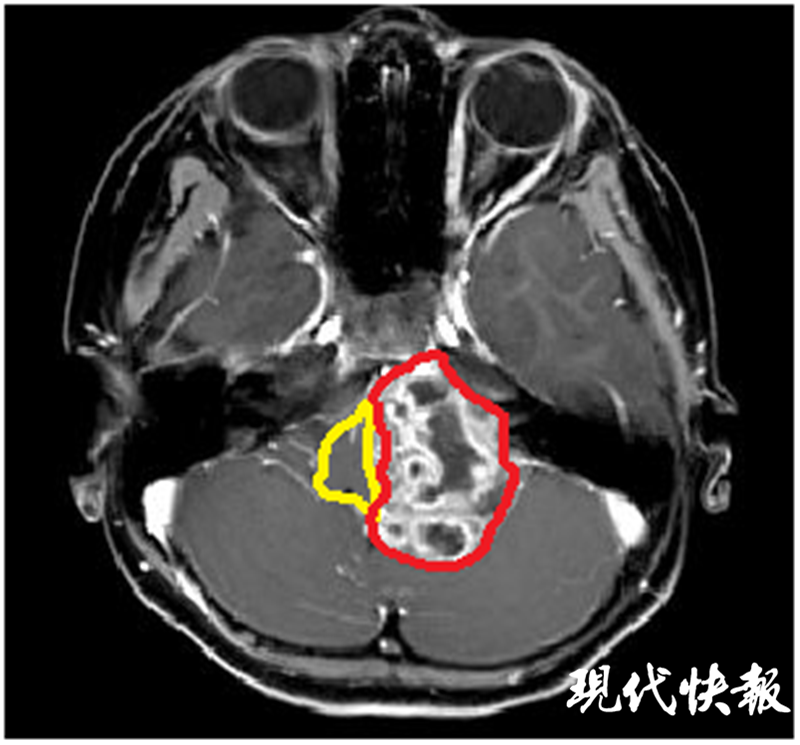

△術(shù)前核磁共振:黃色標(biāo)記為腦干,紅色標(biāo)記為腫瘤

因當(dāng)?shù)蒯t(yī)院無法治療,諾諾父母找到了位于揚(yáng)州的蘇北人民醫(yī)院,向神經(jīng)外科張恒柱教授尋求幫助。經(jīng)過仔細(xì)檢查發(fā)現(xiàn),諾諾顱內(nèi)的腫瘤長徑達(dá)6cm,如雞蛋大小,腦干已被壓縮至正常的1/5,需要盡快手術(shù)治療。但巨大的腫瘤與腦干、小腦緊緊粘連,侵犯左側(cè)后腦幾乎所有的重要血管和神經(jīng),稍有不慎都會導(dǎo)致嚴(yán)重后果。從影像檢查看,諾諾顱內(nèi)腫瘤明顯血管豐富,手術(shù)時(shí)很可能伴隨大出血,而兒童對于出血的耐受能力遠(yuǎn)低于成人。

△術(shù)后核磁共振顯示腫瘤全切,腦干復(fù)位

手術(shù)團(tuán)隊(duì)在術(shù)前反復(fù)討論,制定了最佳的手術(shù)方案,并對手術(shù)中可能出現(xiàn)的各種緊急狀況做了充分準(zhǔn)備。麻醉師、護(hù)士時(shí)刻監(jiān)測,保證了患兒生命體征始終平穩(wěn)。最終,歷時(shí)6個(gè)多小時(shí)的手術(shù),不但成功將諾諾腦內(nèi)的腫瘤完全切除,而且保留了腫瘤周圍所有正常的血管和神經(jīng)。